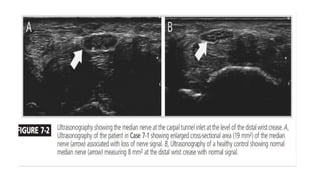

Magnetic resonance imaging (MRI) and ultrasonography :

• Measurements of the canal size.

• Flattening of the nerve at the level of hook of hamate is a usual finding.

• Cross-sectional diameter ratio of median nerve : In normal individuals it should be

one, an increase in the diameter is diagnostic. It is checked at the level of pisiform

to distal radius.

• Fatty infiltration of median nerve

• Bursitis and

• Demonstration of neuroma or other space occupying lesions.

• Incomplete resection of ligament.